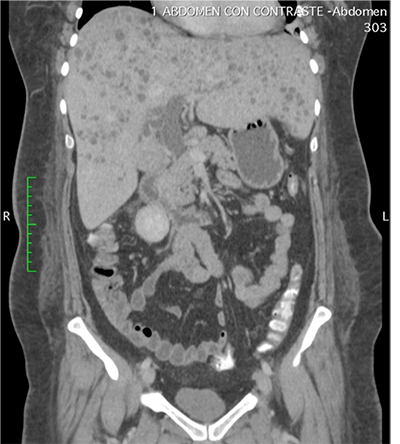

Dentro la evolución del cuadro clínico la paciente presentó una evolución estacionaria, persistiendo con taquicardia, y taquipnea, además de leucocitosis de 19 200 con neutrofolia de 95%, a pesar de haber removido la causa de la obstrucción (coledocolitiasis) y haberse administrado antibióticos (ceftriaxona 1 g EV cada 12 horas y metronidazol 500 mg EV cada 8 horas) durante 72 horas. Es así, que se realiza nueva ecografía abdominal (Figura 2) la cual reportó: “microabscesos hepaticos?, dilatación de vía biliar extrahepática hasta 18 mm y vesícula con barro biliar”, por lo que tras ser valorada por el servicio de medicina interna se decide realizar tomografía axial computarizada (TAC) de abdomen con contraste y en el contexto de una sepsis de foco abdominal por probables microabscesos hepáticos se decide rotar el esquema de tratamiento antibiótico a meropenem 1 g EV cada 8 horas, descontinuando ceftriaxona, y continuando metronidazol 500 mg EV cada 8 horas. En misma fecha se realiza TAC de abdomen con contraste (Figura 3 y 4) la cual reporta: “hepatomegalia, innumerables microabscesos hepáticos, dilatación de vía biliar intra y extrahepatica, a descartar engrosamiento de la pared lateral izquierda de la vesícula biliar, ganglios periportales de etiología por determinar (origen inflamatorio vs metastásico) y mínimo derrame pleural bilateral”. Posteriormente, se solicitan marcadores tumorales de CA 19.9, CA 125, AFP y CEA, todos ellos con resultados dentro de parámetros normales.